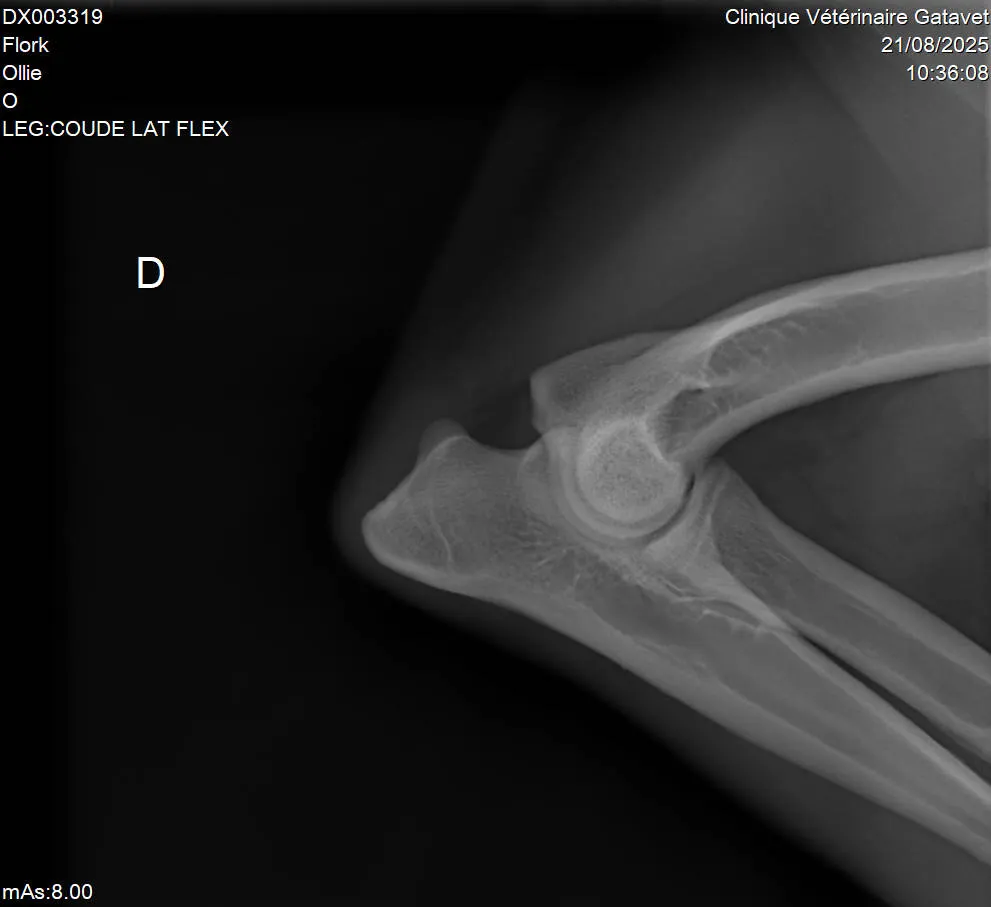

L’apparition de l’arthrose chez le chien survient souvent avec l’âge, mais parfois bien avant. Elle est assez fréquente et peut concerner des chiens jeunes, notamment après un traumatisme, une malformation ou une activité physique intense. Il faut apprendre à la détecter, à la faire diagnostiquer par un vétérinaire, puis à adapter le mode de vie du chien : son alimentation, son environnement et ses exercices. Il faut apprendre à la détecter, à la faire diagnostiquer par un vétérinaire, puis à adapter le mode de vie du chien : son alimentation, son environnement et ses exercices.